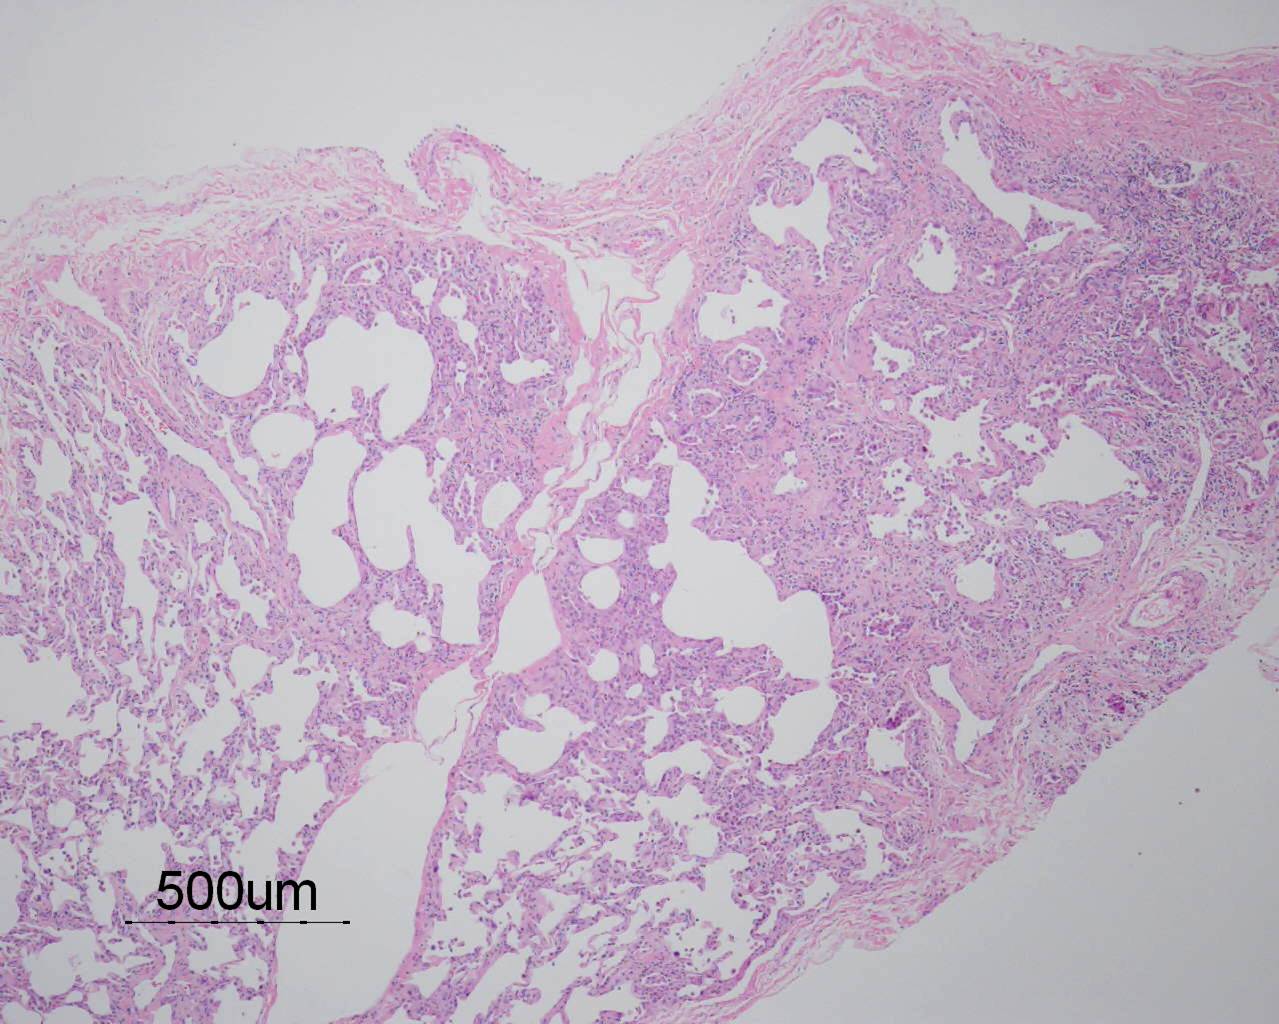

Based on the information found on the CT of the chest, LF underwent an open lung biopsy which showed usual interstitial pneumonitis (UIP) as demonstrated in the pathology below: